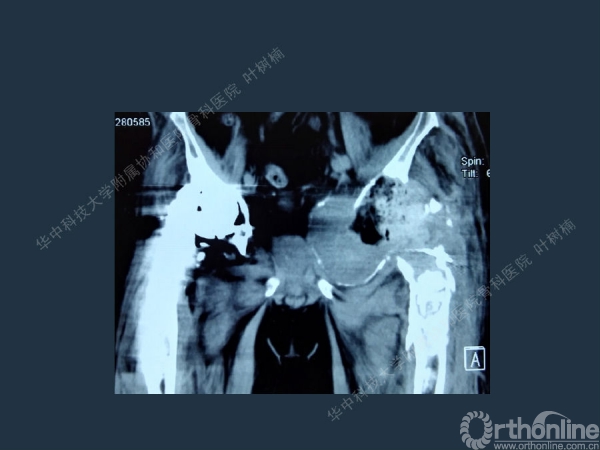

股骨侧翻修

髋臼缺损的处理